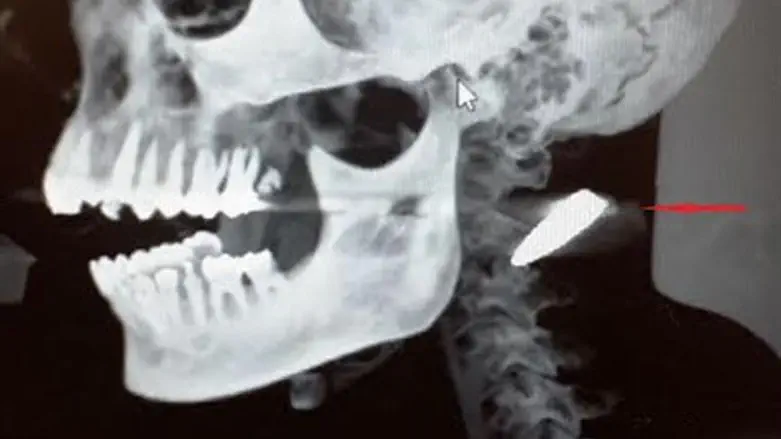

מיד עם תחילת הטיפול בפצוע בחדר הטראומה, הבחינו הרופאים בנפיחות באזור הצוואר, מתחת לאוזן שמאל של הפצוע, אשר עוררה את חשדם. בצילום רנטגן שבוצע, לאחר הבדיקות הראשוניות עם הגיעו של הפצוע התגלה, כי מדובר בקליע רובה, אשר חדר דרך לחיו הימנית, עבר בין הלסת לעמוד השידרה ונעצר מתחת לעור בצד שמאל של צווארו.

הקליע גרם לשבר בלסת העליונה וחתך בחך, אך למזלו של הפצוע הסורי לא פגע בעמוד השידרה ובכלי דם מרכזיים בצוואר.

לאחר שעבר סדרה של צילומי הדמיה, על מנת לשלול אפשרות של פגיעה בחוליות הצוואר או כלי דם גדולים בצוואר, הועבר הפצוע מיידית לחדר הניתוח לניתוח חירום, שכן כל תזוזה של הקליע היתה יכולה לגרום לפגיעה בכלי דם ולהביא לפציעה חמורה ביותר. את הניתוח ביצעו ד"ר אלחנדרו רויזנטול, מנהל היחידה לכירורגיית הפה והלסתות וד"ר מרואן כרם, רופא בכיר במחלקת אף-אוזן-גרון.